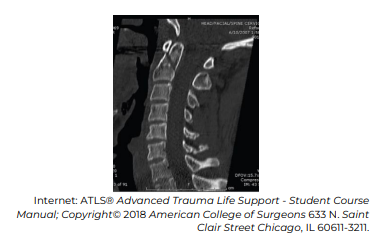

Considerando o caso hipotético apresentado e seu diagnóstico, assinale a alternativa correta relacionada à classificação do achado radiológico e à droga envolvida na PCR, respectivamente.